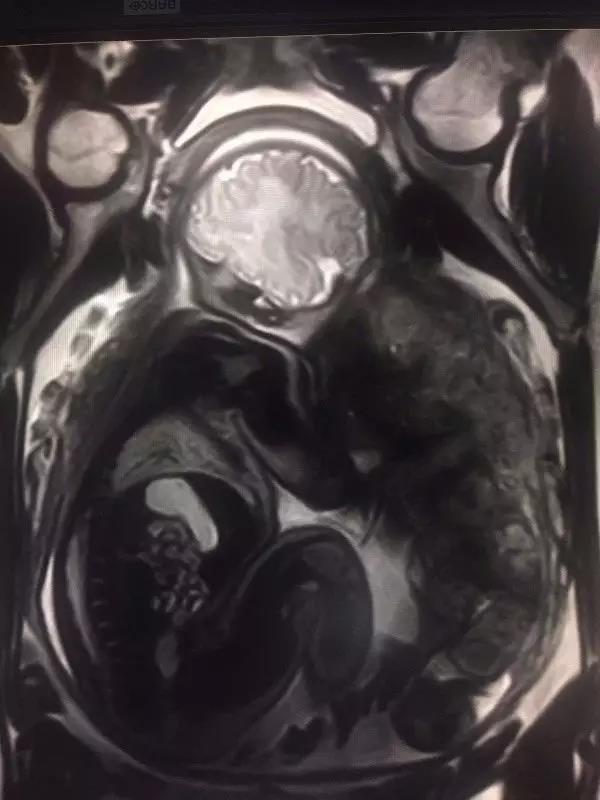

A:当然可以,一般胎儿我们建议孕期3个月以上孕妇检查,彩超在胎儿筛查中最常用,但是如果某些胎儿病变或者发育异常彩超无法明确时,磁共振就成了我们的不二选择;对于心脏的MRI检查技术已经相当成熟,我科有专业团队负责扫描与诊断,而且常常在CT上才能做的冠脉成像,在我们MRI上也可以完成,并且无需注射造影剂。

上图分别为胎儿头颅及胎盘成像